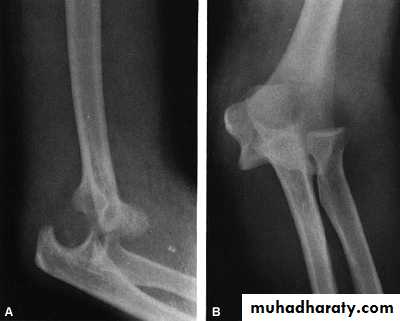

Elbow dislocation

Fall on outstretched hand

Posterior or posterolateral

Simple or complex

Reduction

TractionGradual flexion

Don`t immobilize the elbow > 3w